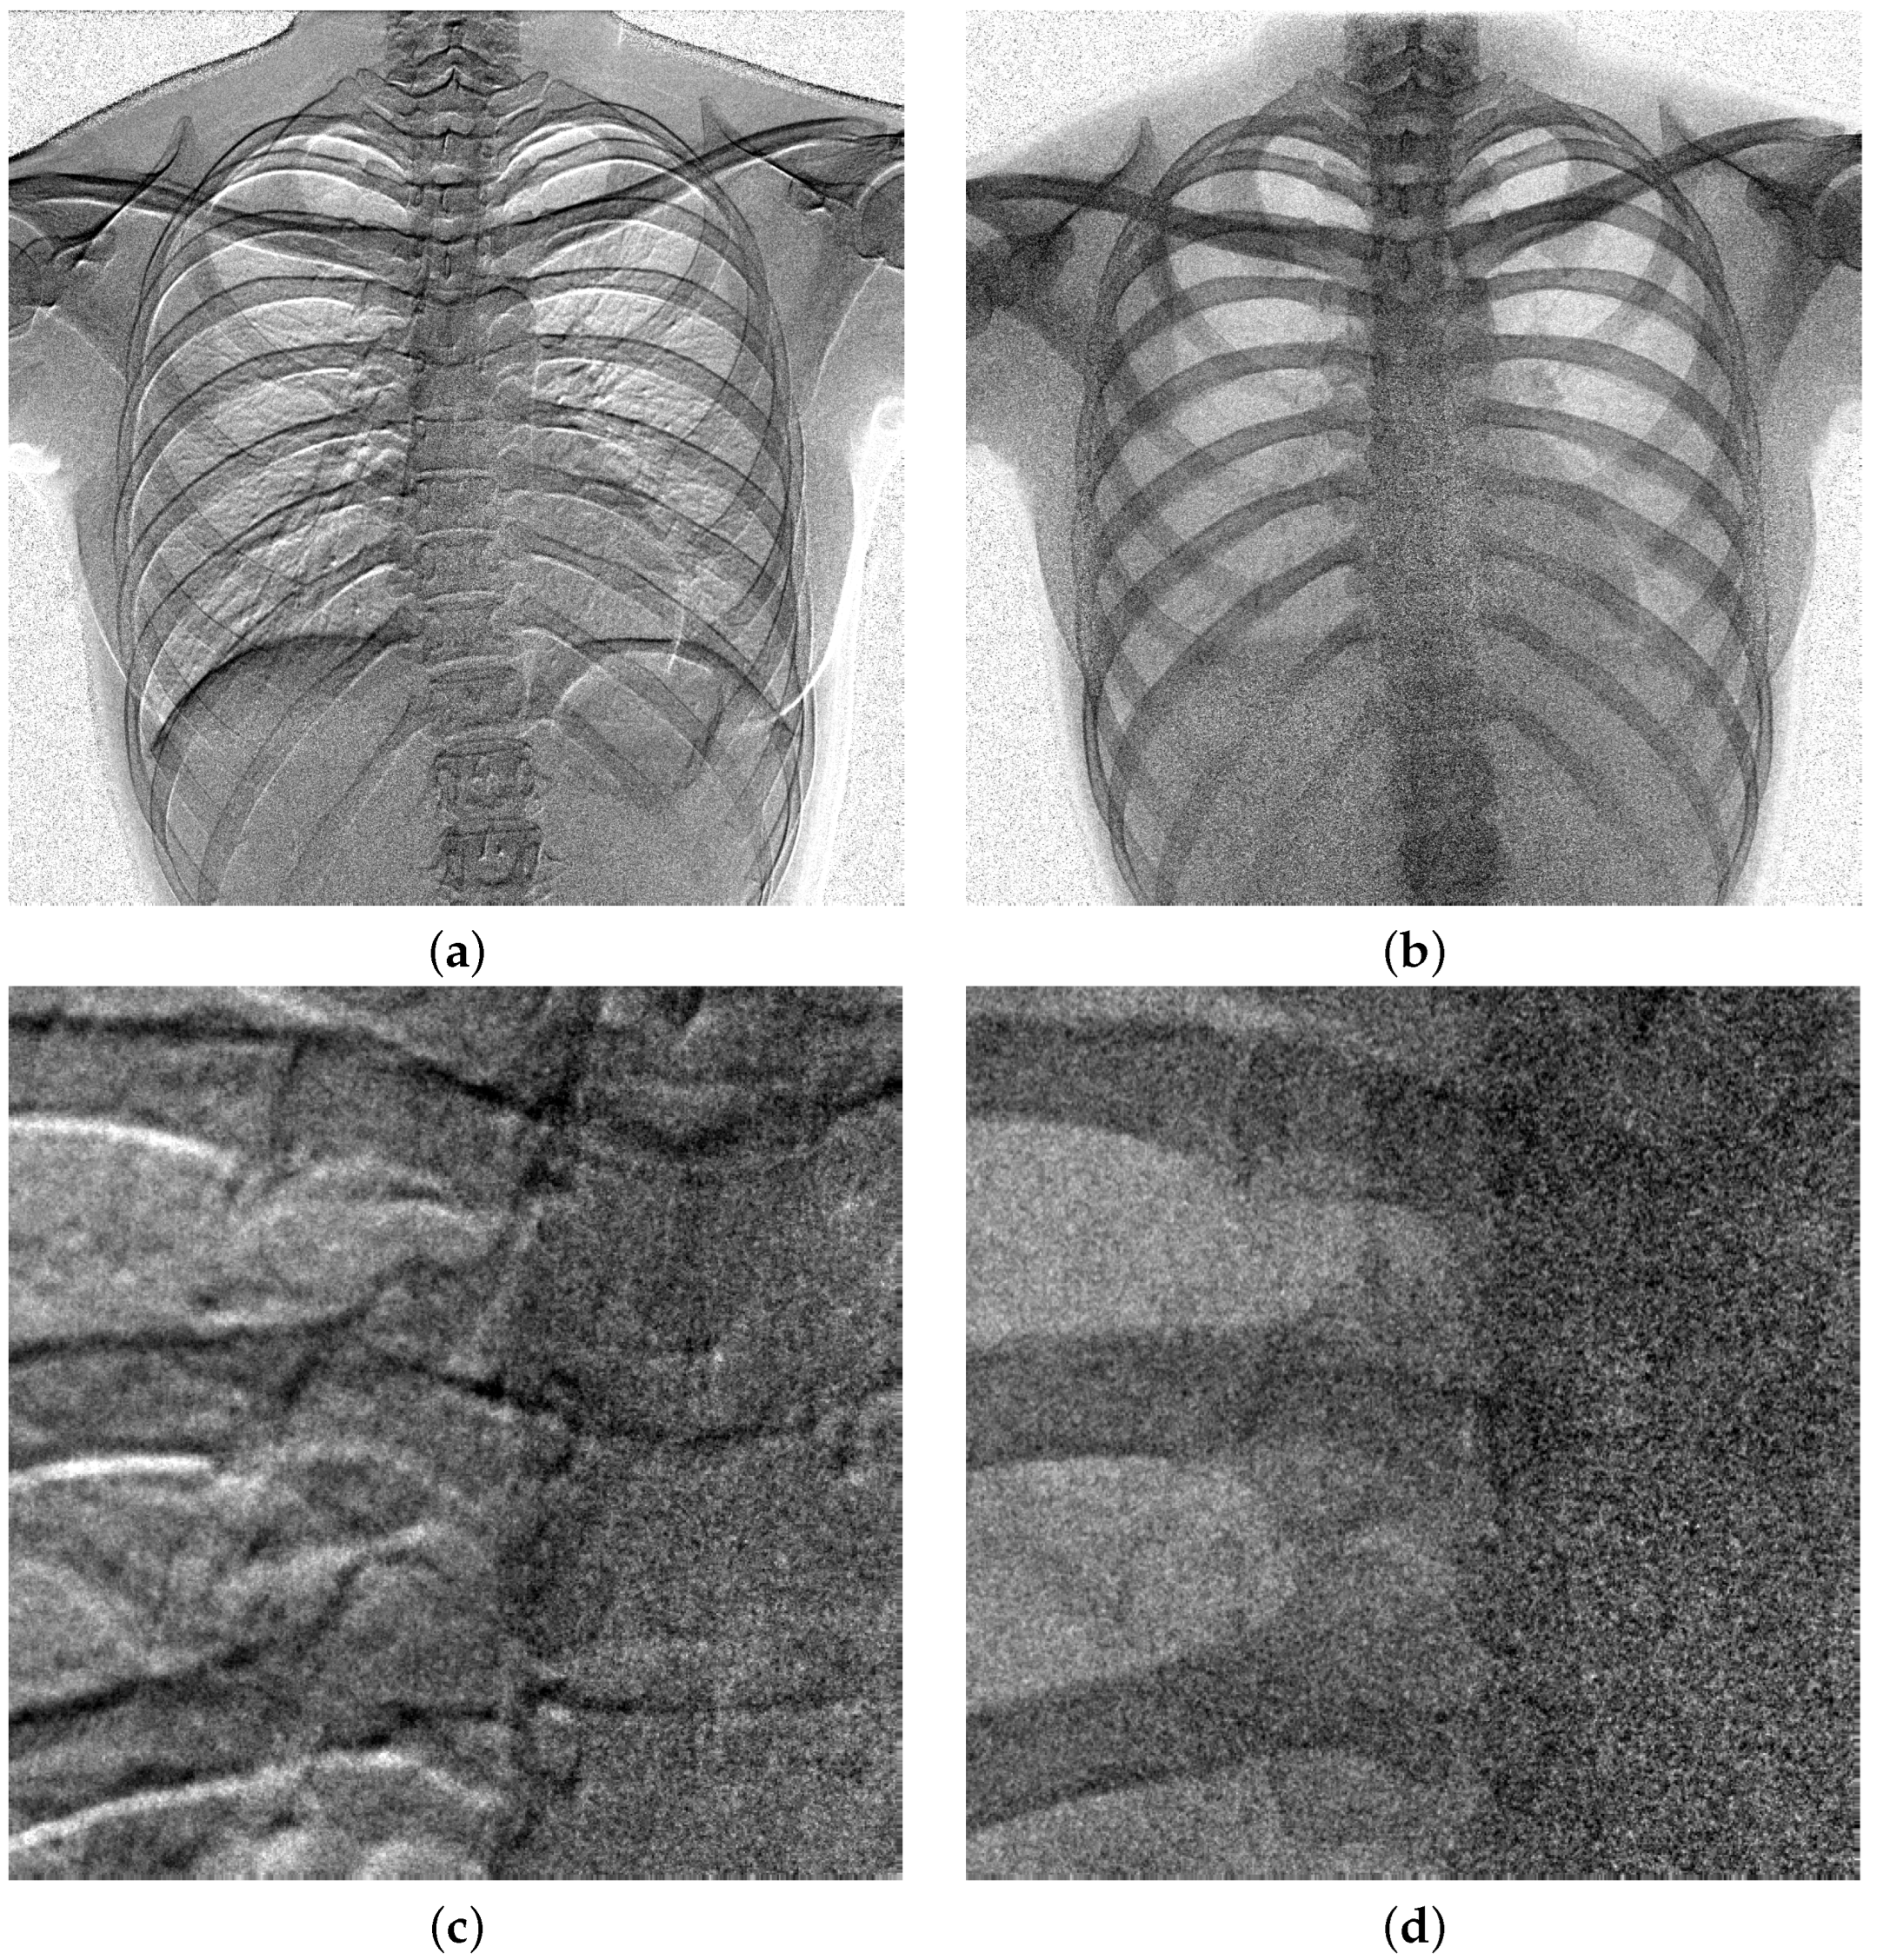

4.1. Alignment of Lower Images